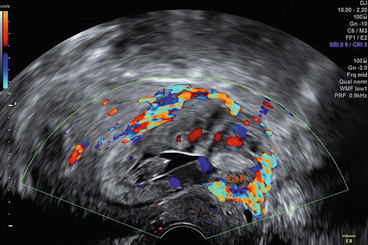

Correct ultrasound diagnosis is essential to differentiate between these types of ectopic pregnancies. It is even more important to differentiate them from a normal intrauterine pregnancy or inevitable miscarriage in order to avoid serious complications. The first ultrasound criterion for diagnosis is identifying the gestational sac or trophoblastic tissue at or below the level of the internal os with a clear invasion into the myometrium. Sliding organ sign will be negative as the gestational sac cannot be displaced from its surrounding. Another important ultrasound feature is the high blood flow (>20 cm/s) in the peritrophoblastic circulation on colour Doppler examination. This is different to inevitable miscarriage where the gestational sac usually changes position on applying gentle pressure with the ultrasound probe with no evidence of trophoblastic blood flow in the nearby myometrium [38, 60

,

74

] (Figs. 13.11, 13.12, 13.13, 13.14 and 13.15).

Fig. 13.11

Early Caesarean scar ectopic pregnancy

Fig. 13.12

Caesarean scar ectopic pregnancy